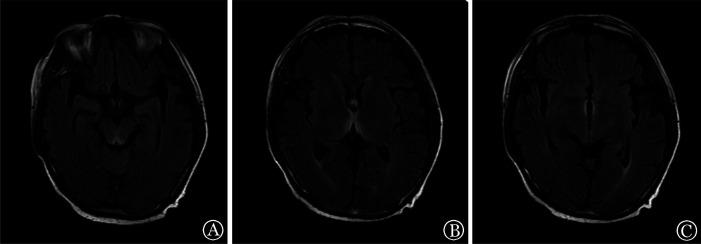

Case 1: A 27-year-old female with ALK-positive anaplastic large cell lymphoma/leukemia; Case 2: A 27-year-old male with acute myeloid leukemia; Case 3: A 56-year-old male with myelodysplastic syndrome. These three patients underwent haploid hematopoietic stem cell transplantation and experienced severe oral mucosal inflammation, nausea, vomiting, diarrhea, and other symptoms over a long period, which significantly restricted eating. Neurological and psychiatric symptoms appeared at 50, 38, and 50 days following transplantation, respectively. The diagnosis of Wernicke encephalopathy was made by head magnetic resonance imaging, whereas the condition improved significantly after intravenous infusion of vitamin B(1).

病例1:一名27岁的ALK阳性间变性大细胞淋巴瘤/白血病女性;病例2:一名27岁的急性髓系白血病男性;病例3:一名56岁的骨髓增生异常综合征男性。这三名患者接受了单倍体造血干细胞移植,长期出现严重的口腔黏膜炎症、恶心、呕吐、腹泻等症状,严重限制了进食。分别在移植后50天、38天和50天出现神经和精神症状。通过头部磁共振成像诊断为韦尼克脑病,静脉输注维生素B1后病情明显改善。